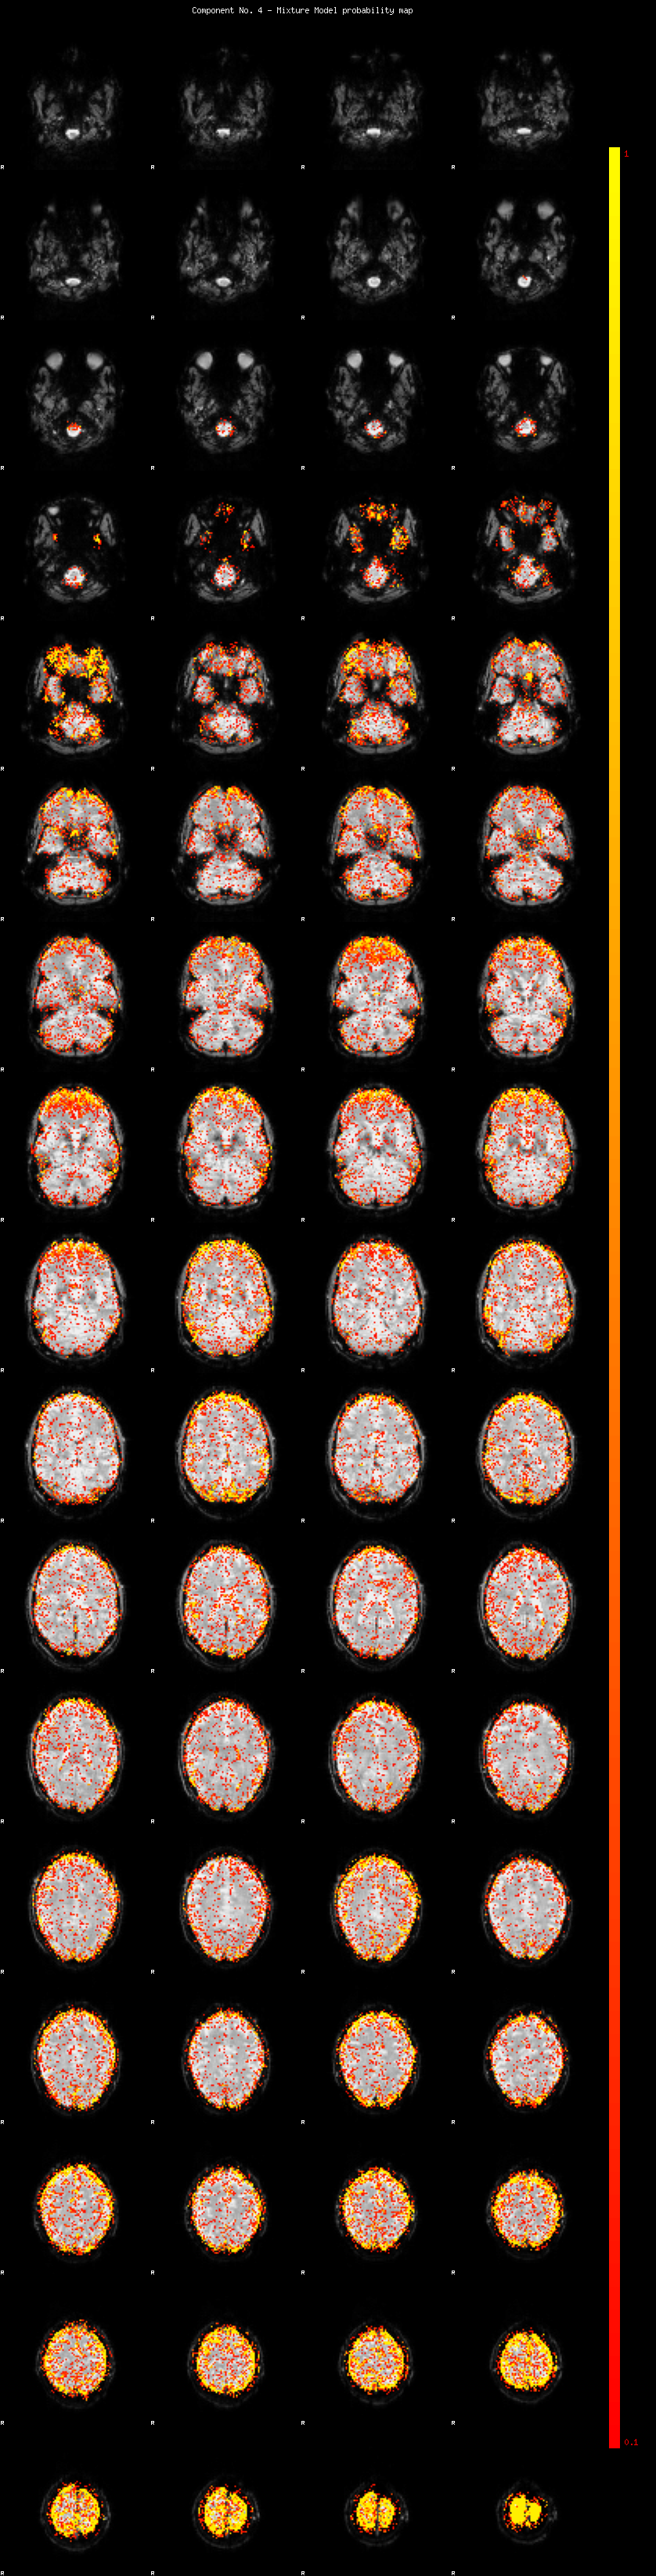

IC_4 Mixture Model fit

Means : 0.000000 3.367761 -2.608594

Vars : 1.000000 5.253775 2.387576

Prop. : 0.865352 0.077052 0.057597